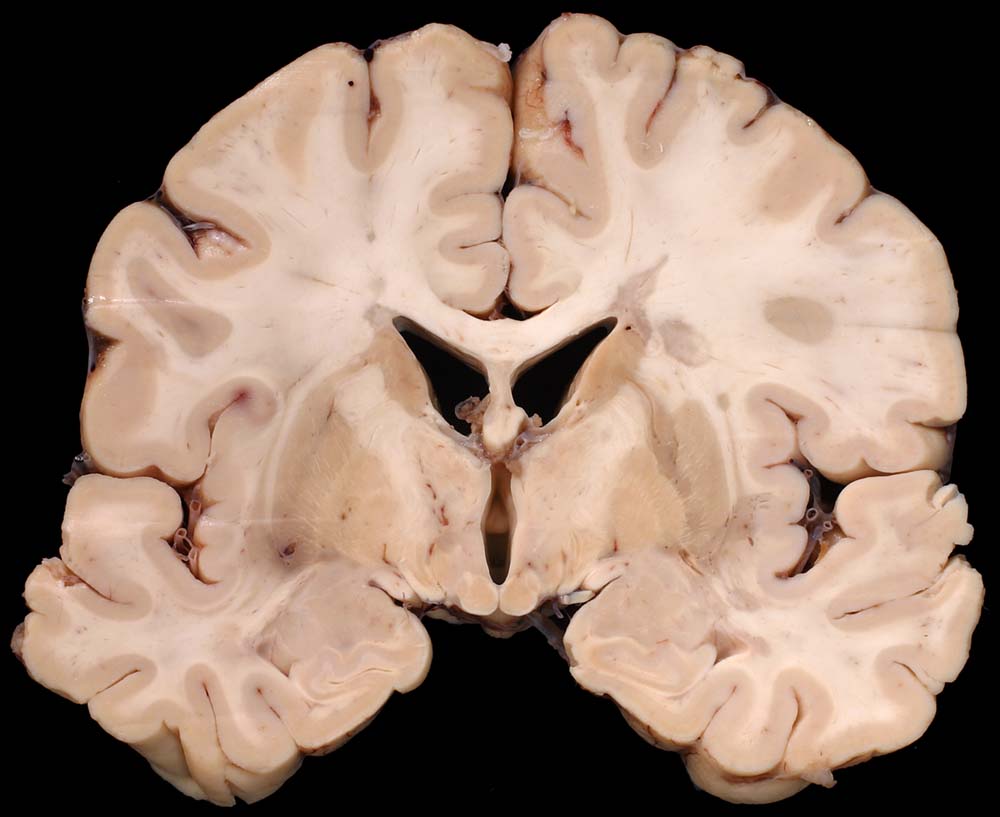

An Frontalschnitten durch das Gehirn fallen makroskopisch Entmarkungsherde vor allem im unmittelbar periventrikulären Marklager auf (um die Vorderhörner, die Cella media und um die Hinterhörner). Nicht selten finden sie sich auch um den Aquädukt und am Boden des 4. Ventrikels. Die Farbe der Herde hängt vom Alter des Prozesses ab (eher rosa bei frischen, eher grau bei alten Herden), die Konsistenz ist weich bei frischen, zunehmend derb bei alten Herden durch Gliafaservermehrung. Histologisch zeigen frische Entmarkungsherde in den ersten Tagen eine Oligodendrogliavermehrung. Ihr folgt mit beginnendem Markabbau eine Mikrogliareaktion. Mikrogliazellen, Monozyten und Makrophagen phagozytieren die Markscheidenzerfallsprodukte (> 10160) (> 10159), die teilweise lichtmikroskopisch im Zytoplasma erkennbar sind (> 10161). Lymphozyten und Plasmazellen sind vor allem perivenös an den Herdrändern lokalisiert. Zusätzlich proliferieren faserbildende Astrozyten (> 10162). In älteren Herden (vorliegendes Präparat) fehlen die Markscheiden praktisch vollständig. Axone bleiben erhalten und es besteht eine dichte Fasergliose. Diese ausgebrannten Herde überwiegen beim chronisch Erkrankten. Auch bei ihm können allenfalls noch frischere Stadien gefunden werden.

Makroskopie

Befund

Pathologischer Befund

Normalbefund